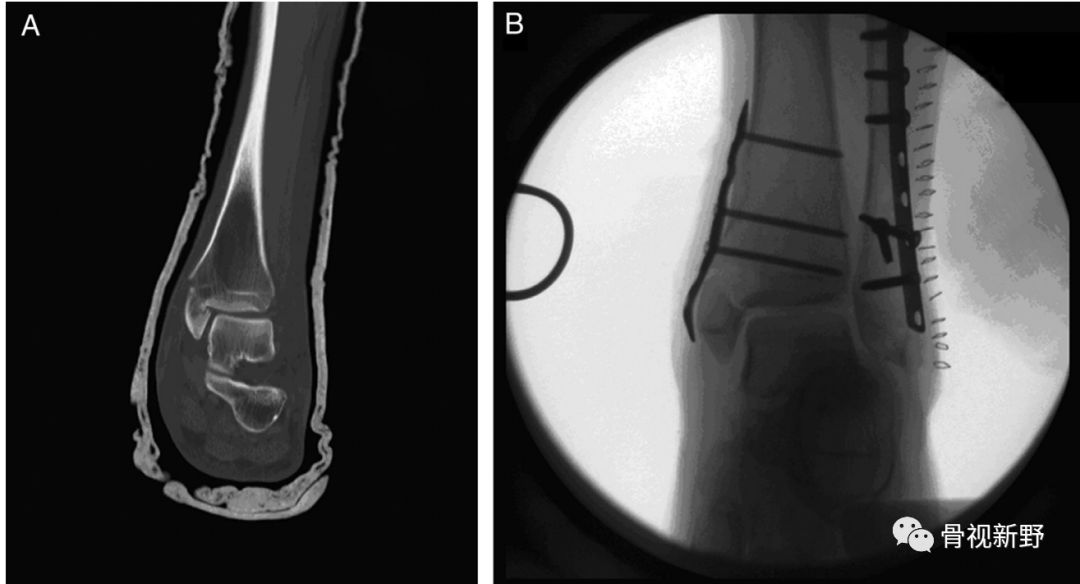

内踝垂直型骨折的buttress固定

内踝骨折根据骨折线走形方向可分为:横形、斜形、粉碎、垂直骨折,其中斜形、垂直形,特别是垂直型骨折的剪力较大,常规克氏针、空心钉、张力带等固定措施不能很好中和剪切力,应用buttress钢板的防滑原理可减少不愈合及畸形愈的并发症。

后踝/后Pilon骨折的buttress固定

后踝骨折和后Pilon骨折的界限一直不是很清楚。一般认为旋转性损伤机制、骨折块小、没有压缩的胫骨远端后方骨折属于后踝骨折,而跖屈损伤机制、骨块大、有压缩者往往属于后Pilon骨折。不稳定、较大骨块的后踝骨折及后Pilon骨折用空心钉固定有可能不能很好地中和向上的剪力,可选择butress钢板作防滑固定,以对抗垂直剪力。